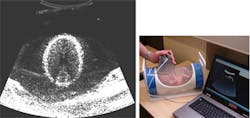

A low-cost scanner that can be plugged into any computer or laptop to reveal vital information about an unborn child has been developed by engineers at Newcastle University (Newcastle, UK).

The hand-held USB device -- which is roughly the size of a computer mouse -- works in a similar way to existing ultrasound scanners, using pulses of high frequency sound to build up a picture of the unborn child on a computer screen.

However, unlike the technology used in most hospitals across the UK costing anywhere from £20,000-£100,000, the scanner created by Jeff Neasham and research associate Dave Graham at Newcastle University can be manufactured for as little as £30-40.

Tested by researchers in the Regional Medical Physics Department at the Freeman Hospital, part of the Newcastle upon Tyne Hospitals NHS Foundation Trust, the scanner produces an output power that is 10-100 times lower than conventional hospital ultrasounds.